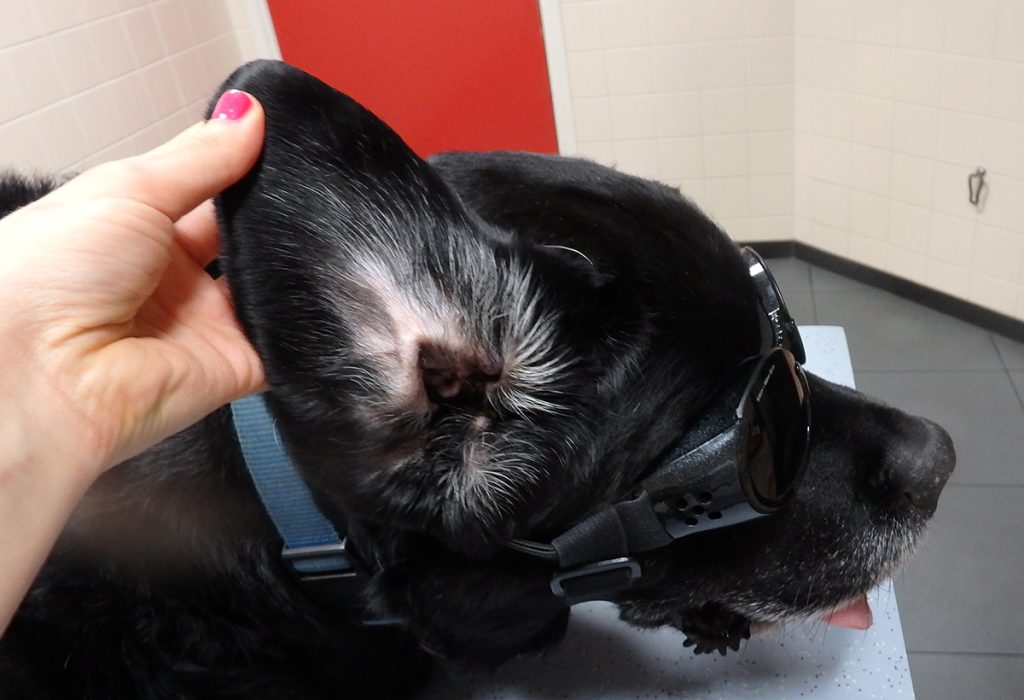

Wanneer zo’n bloedvat beschadigd, ontstaat een bloeding waarbij de huid van het kraakbeen gedrukt wordt. Dit zorgt voor een verdikking van de oorschelp; het karakteristieke beeld van een bloedoor. Een bloedoor ook wel othematoom genoemd zien we het meest bij de hond, maar soms ook bij de kat.

De meest voorkomende oorzaak van een bloedoor is oorontsteking. Door de pijn en jeuk aan het ontstoken oor zal de hond gaan krabben of met zijn kop schudden en met zijn oren klapperen. Wanneer het oor hard genoeg klappert kan een bloedvat kapot gaan. Maar ook krabben, bijten of stomp trauma kunnen een bloeding en daarmee een bloedoor veroorzaken.

Het is dan ook verstandig om het afwijkende oor te laten beoordelen door uw dierenarts. En wanneer de onderliggende oorzaak een oorontsteking is, moet deze natuurlijk ook behandeld worden, zodat het dier minder de neiging heeft tot krabben/flapperen.

De derde optie is de laserbehandeling. Met lasertherapie wordt de genezingstendens verbeterd en de kwaliteit van het bindweefsel verbeterd. Dit zorgt voor minder of geen vorming van een bloemkooloor en dus minder of geen pijnlijkheid.